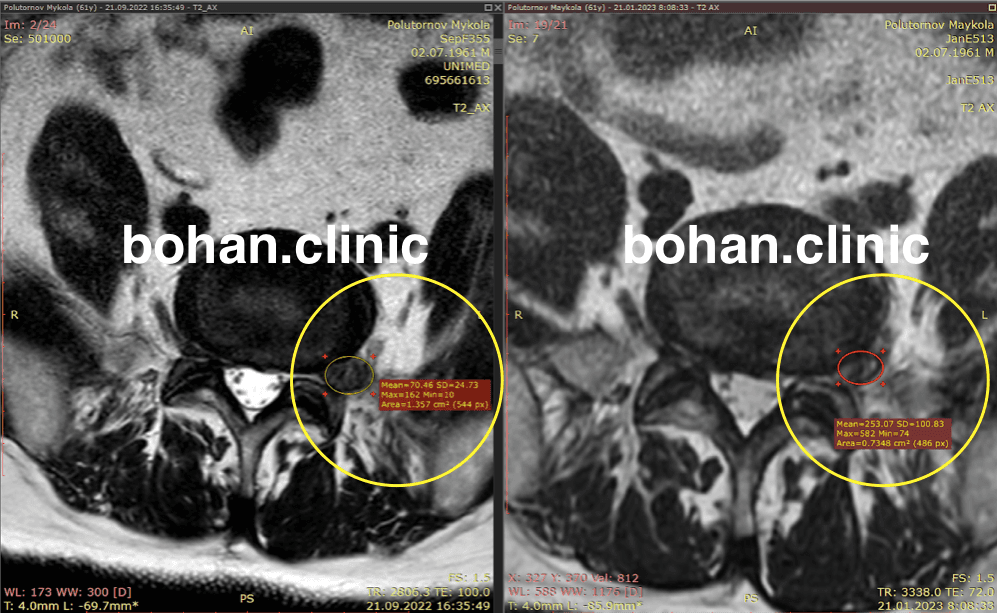

Метод лікування грижі шляхом стимуляції резорбції в Україні був впроваджений у 2020-2021 роках.  Алгоритм оцінки грижі на предмет резорбції, що використовується у клініках – є авторським, розроблений лікарем Боханом А.Ю.